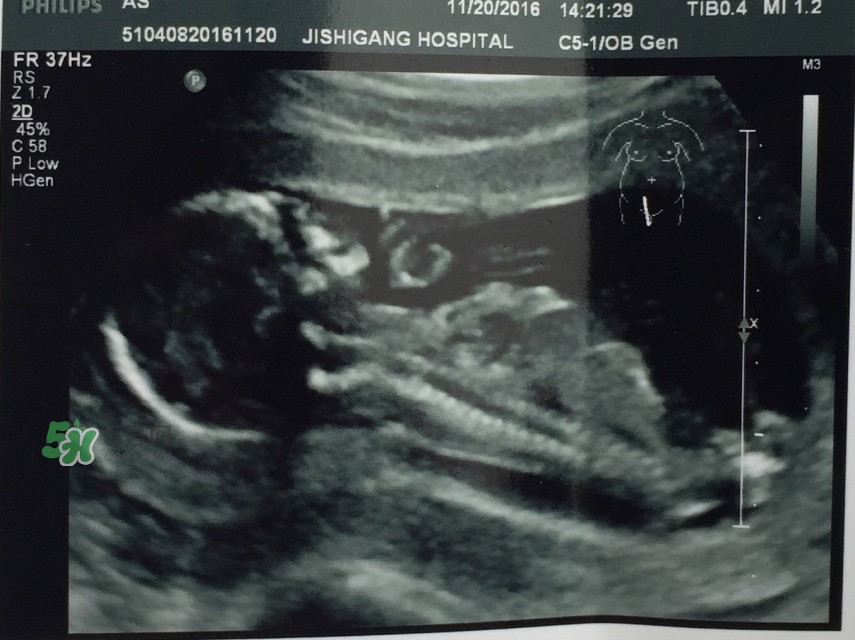

* 2016年11月20日孕15w

建卡后第一次孕檢,B超,尿檢,醫(yī)生說太早吃鈣片,停吃10天

愛博爾四維彩超,愛吃手指、愛摸屁屁的萌寶寶